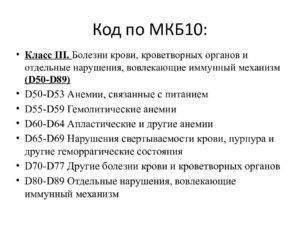

Код мкб 10 атерома головы

Код мкб 10 атерома головы 109 фото